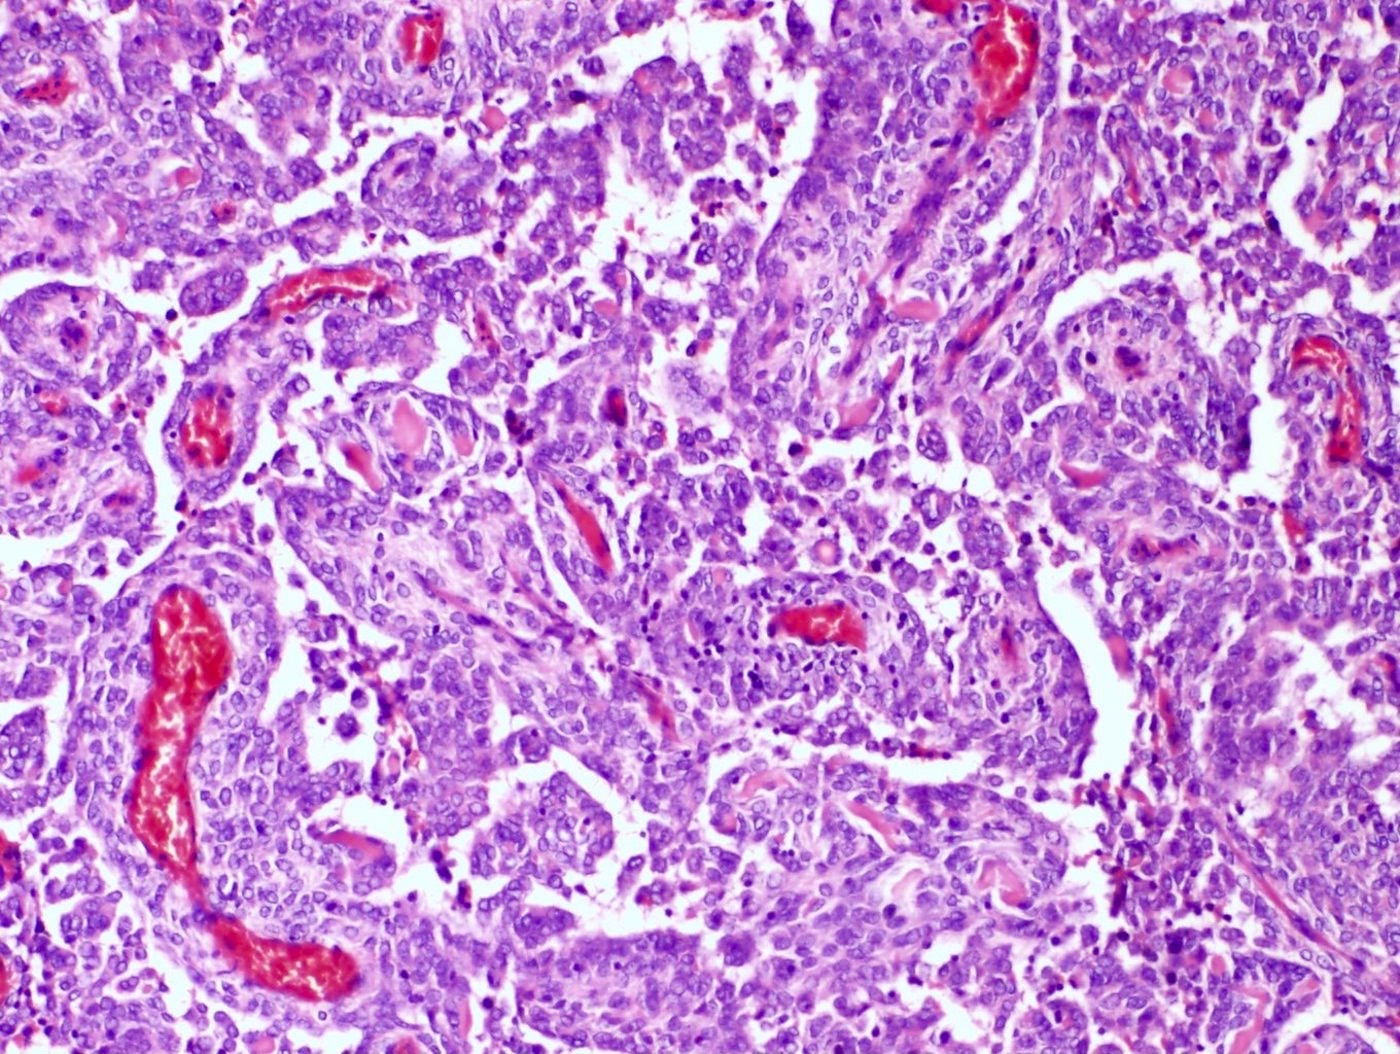

Microscopic (histologic) description

- Irregular cellular islands, forming permeative tongue-like pattern of myometrial invasion with frequent vascular invasion

- May have smooth muscle differentiation, particularly in a starburst morphology, with collagen bands radiating towards the periphery of the nodule

- Other reported types of differentiation: fibromyxoid / fibrous, sex cord-like, epithelioid, rhabdoid, endometrioid glands, pseudopapillae, clear cells, bizarre cells, adipose tissue (Mod Pathol 2016;29:S92)

Microscopic (histologic) images

Contributed by Elizabeth Kertowidjojo, M.D., Ph.D., M.P.H. and Ayse Ayhan, M.D., Ph.D.